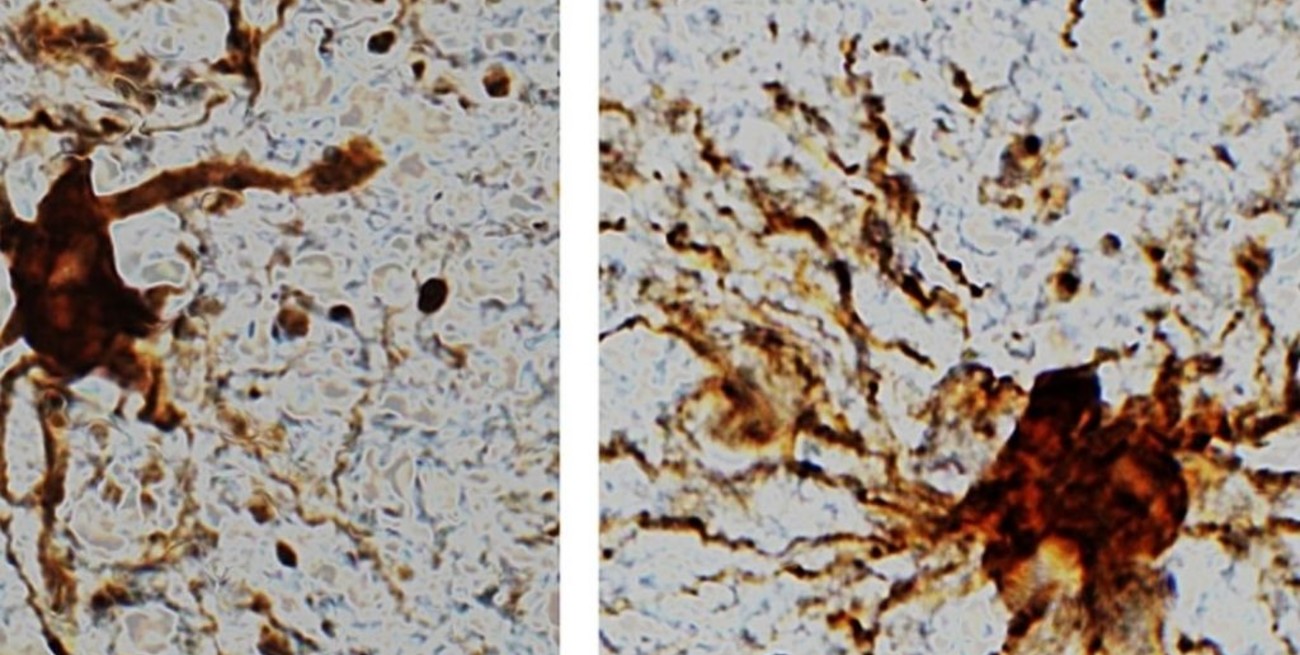

Además, encontraron un tipo específico de "genes zombis", que aumentan su actividad tras la muerte, alcanzando los niveles máximos aproximadamente 12 horas después del deceso. Se asocian con las células gliales, que junto con las neuronas forman parte del tejido nervioso, donde tienen una función auxiliar.

El fenómeno por sí solo "no es demasiado sorprendente", comentó uno de los autores del estudio, Jeffrey Loeb, en un comunicado de la Universidad de Illinois en Chicago. "[Las células gliales] son inflamatorias y su trabajo es limpiar las cosas después de producirse lesiones cerebrales, como la falta de oxígeno o un derrame cerebral", indicó el científico.